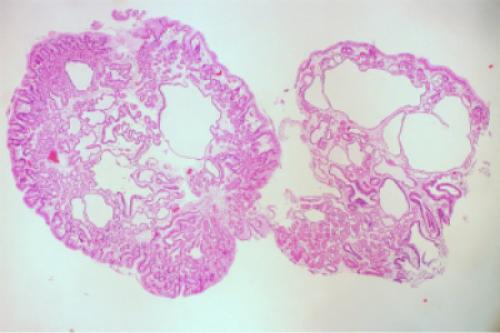

Грибовидные и полиповидные образования относятся к редким патологиям. Их диагностируют примерно в 3% от общего числа выявленных карцином желудка. Такие опухоли обычно красного цвета, дольчатые, возвышаются над поверхностью, имеют четкие границы. Размер образования может быть разным. Полипозный рак — это образование в виде полипа, имеющего тонкую ножку. Грибовидный рак — это опухоль в виде соцветия цветной капусты с широким основанием. Поверхность таких образований может быть покрыта эрозиями, участками с кровоизлияниями и скоплениями фибрина. Гистологическое строение полиповидного рака — папиллярная аденокарцинома, грибовидного — недифференцированный рак.

Блюдцеподобный рак диагностируется примерно в 30% случаев, имеет вид распавшегося образования экзофитного типа (язва с широким основанием и четкими границами). Гистологическое строение — аденокарцинома.

- первый вид рака желудка (Тип 1) – полиповидный или грибовидный – в форме гриба, бляшки, полипа – отчетливо отделяется от здоровой ткани и имеет ножку;

- второй вид рака желудка (Тип 2) – экзофитный изъязвленный или блюдцеобразный у такого рака желудка края приподняты, а границы четко очерчены. Этот тип заболевания – деструктивная стадия грибо- и полиповидного рака;